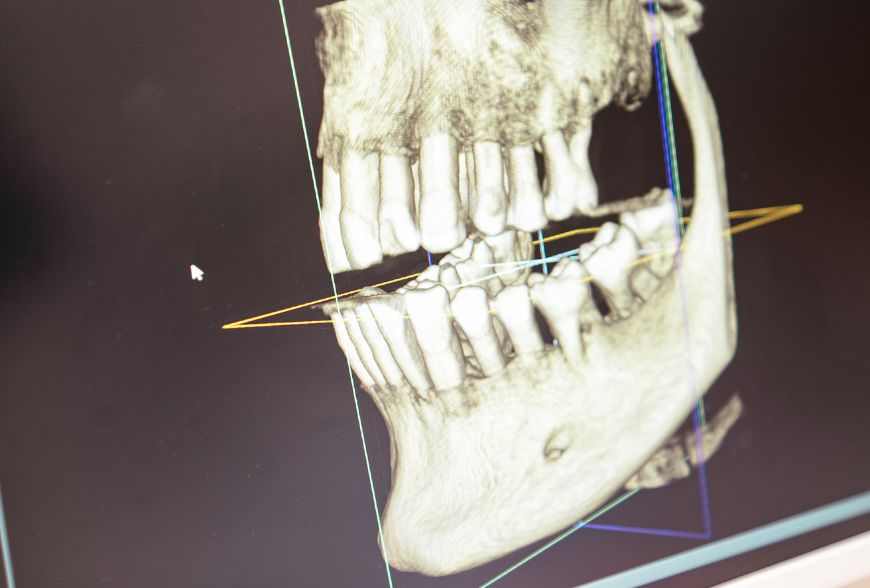

Una corona dental es una prótesis fija que se coloca sobre el diente natural para dar una solución a un problema dental. Actúan como funda que recubre completamente el diente, devolviéndole funcionalidad, estética y protección frente a futuros daños.

En los implantes dentales, la corona es una parte visible que sustituye al diente natural. Se fija sobre el implante y cumple una función tanto estética como masticatoria, integrándose de forma natural con el resto de la dentadura.